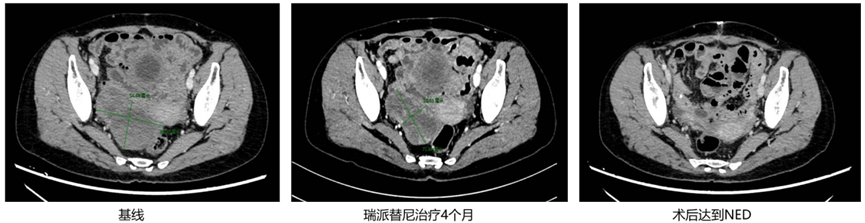

病例三

基本情况

患者,女,57岁,2015年因腹痛就诊,确诊为小肠GIST,高危险度。

既往手术及一线治疗

◈ 2015年行首次手术,术后服用伊马替尼2月后停药,期间未行规律复查。

◈ 2019年因肠梗阻行手术治疗,术后规律服用伊马替尼400 mg qd。

◈ 2025年3月4日,CT示右侧附件区见类圆形团块影,较大约86mm×55mm,增强呈轻度强化。

◈ 2025年3月12日,基因检测结果示KIT 外显子17 N822Y突变。

二线治疗

◈ 2025年3月28日,开始服用瑞派替尼150 mg qd。

◈ 2025年5月27日,CT示右侧附件区混杂低密度影,增强可见不均匀强化,大小约为67mm×58mm,肿瘤缩小并接近PR,综合考虑决定再继续服用瑞派替尼。

◈ 2025年7月22日,瑞派替尼治疗4个月后进行评估,肿瘤未再次缩小(约为74mm×38mm),进行综合评估后,已达到手术标准,遂于2025年7月30日行“盆腔病损切除术+肠粘连松解术”,术后达到NED,继续服用瑞派替尼150 mg qd。